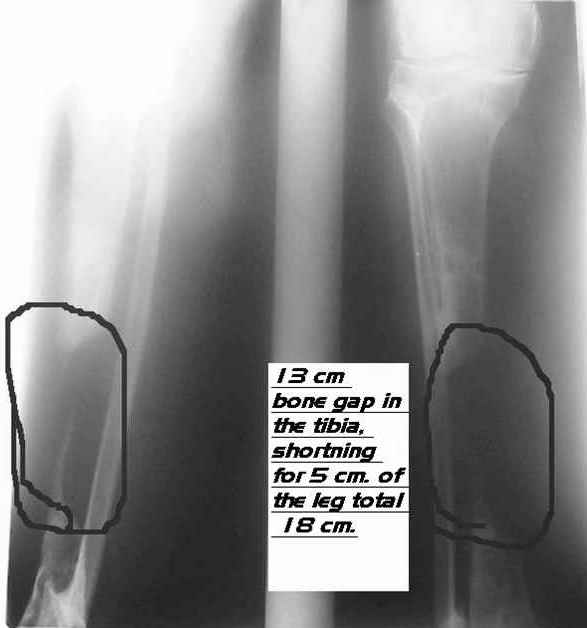

It is difficult to see on the xr you sent, but it seems that proximal and distal metaphysis are also involved and the bone there is not of good quality too do a bifocal convergent transport.

Alternative will be to do a medial transport of half or of the all fibula after ressection of all bad quality bone as on the attached scketch.